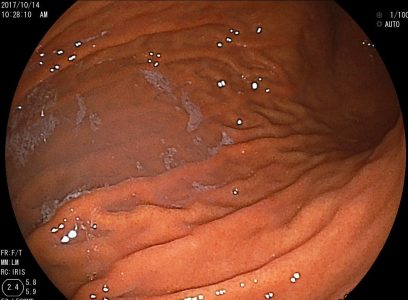

(1) 위내시경 검사

위축성 위염의 기본적인 진단은 위내시경 검사를 통해 이루어집니다. 내시경 검사 시 다음과 같은 특징적인 소견이 관찰됩니다:

- 위점막이 얇아진 상태

- 점막의 창백함

- 점막의 반짝거림

- 점막 아래 혈관이 투명하게 보임

- 위 주름의 감소